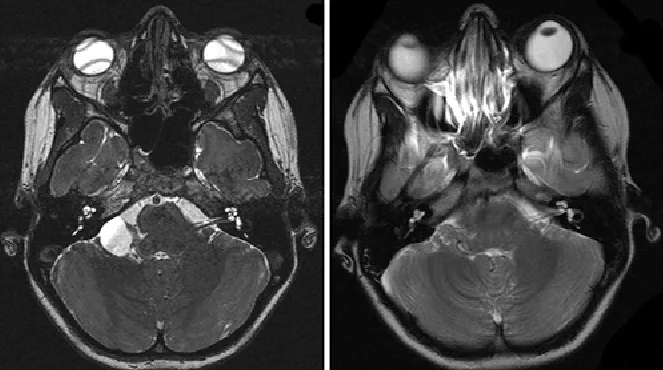

对于这类患者,手术并非简单的囊肿剔除,而是需要在保护重要神经结构和彻底缓解症状之间找到平衡点。Di Rocco教授团队采用的手术策略包括:首先,通过术中神经电生理监测实时评估第七、八对脑神经的功能状态,这使得医生能够在操作过程中随时调整策略,避免进一步伤害。其次,选择恰当的手术入路——通过影像学数据精确定位囊肿与周围神经血管的关系,制定个体化的手术方案。第三,术后的影像学复查(MRI对比)显示,虽然囊肿被成功切除或部分引流,但患者的神经结构和脊液通道得到了明显改善。

对于儿童听力缺损患者,临床医生需要保持高度警觉。传统的听力检查(纯音测听、脑干听觉诱发电位ABR)能够确认听力损失的存在,但要找到真正的病因,高分辨率MRI(尤其是T2加权序列)是必不可少的。Di Rocco教授团队的案例表明,很多家长在带孩子做过普通听力检查后就放弃了进一步诊查。这是一个常见的误区。当儿童出现原因不明的听力下降时,颅内病变(包括桥小脑角区囊肿)必须被列入鉴别诊断的范围。